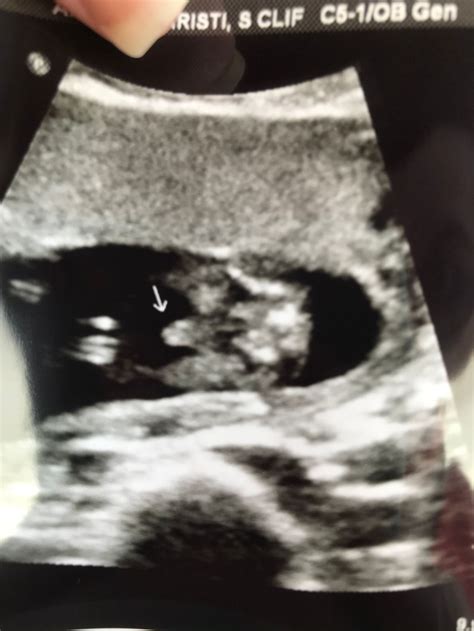

Understanding the Ultrasound Images

The 16 week ultrasound provides detailed images of the baby’s anatomy. Healthcare providers will look for specific features to ensure everything is developing normally. Some of the key areas of focus include:

• Head and Brain: The shape and size of the head, as well as the development of the brain structures.

• Heart: The structure and function of the heart, including the four chambers and major blood vessels.

• Spine: The alignment and development of the spinal column.

• Limbs: The length and structure of the arms and legs, including the hands and feet.

• Abdominal Organs: The development of the stomach, intestines, kidneys, and bladder.